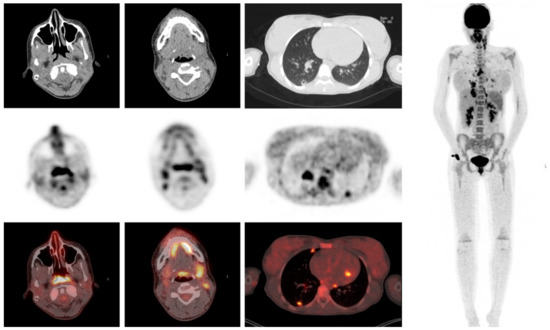

3.6. Clinical Examples